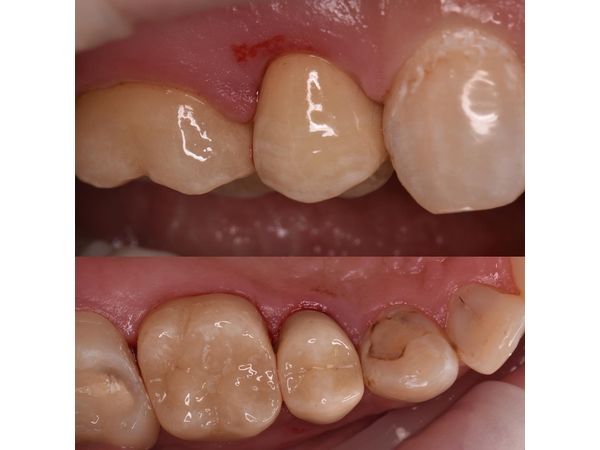

- Зафиксировали керамические реставрации (постоянные коронки).

После проведённого лечения у пациентки пропали все неприятные симптомы, она снова могла нормально жевать.

На контрольном осмотре через полгода девушку ничего не беспокоило. Изготовленные коронки были в хорошем состоянии. Пациентке рекомендовали сделать профессиональную гигиену полости рта.